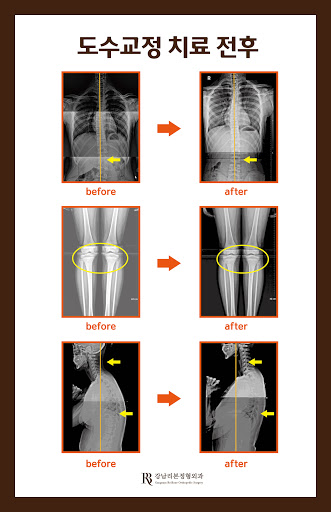

코멘트: #춘천무릉공원풋살장 주차장#혜윤빌딩 1층.#강남리본정형외과#통증크리닉.#척추.#어께.#관절.#수지족부외상#골다공증.#성장.#비만.#도수치료.